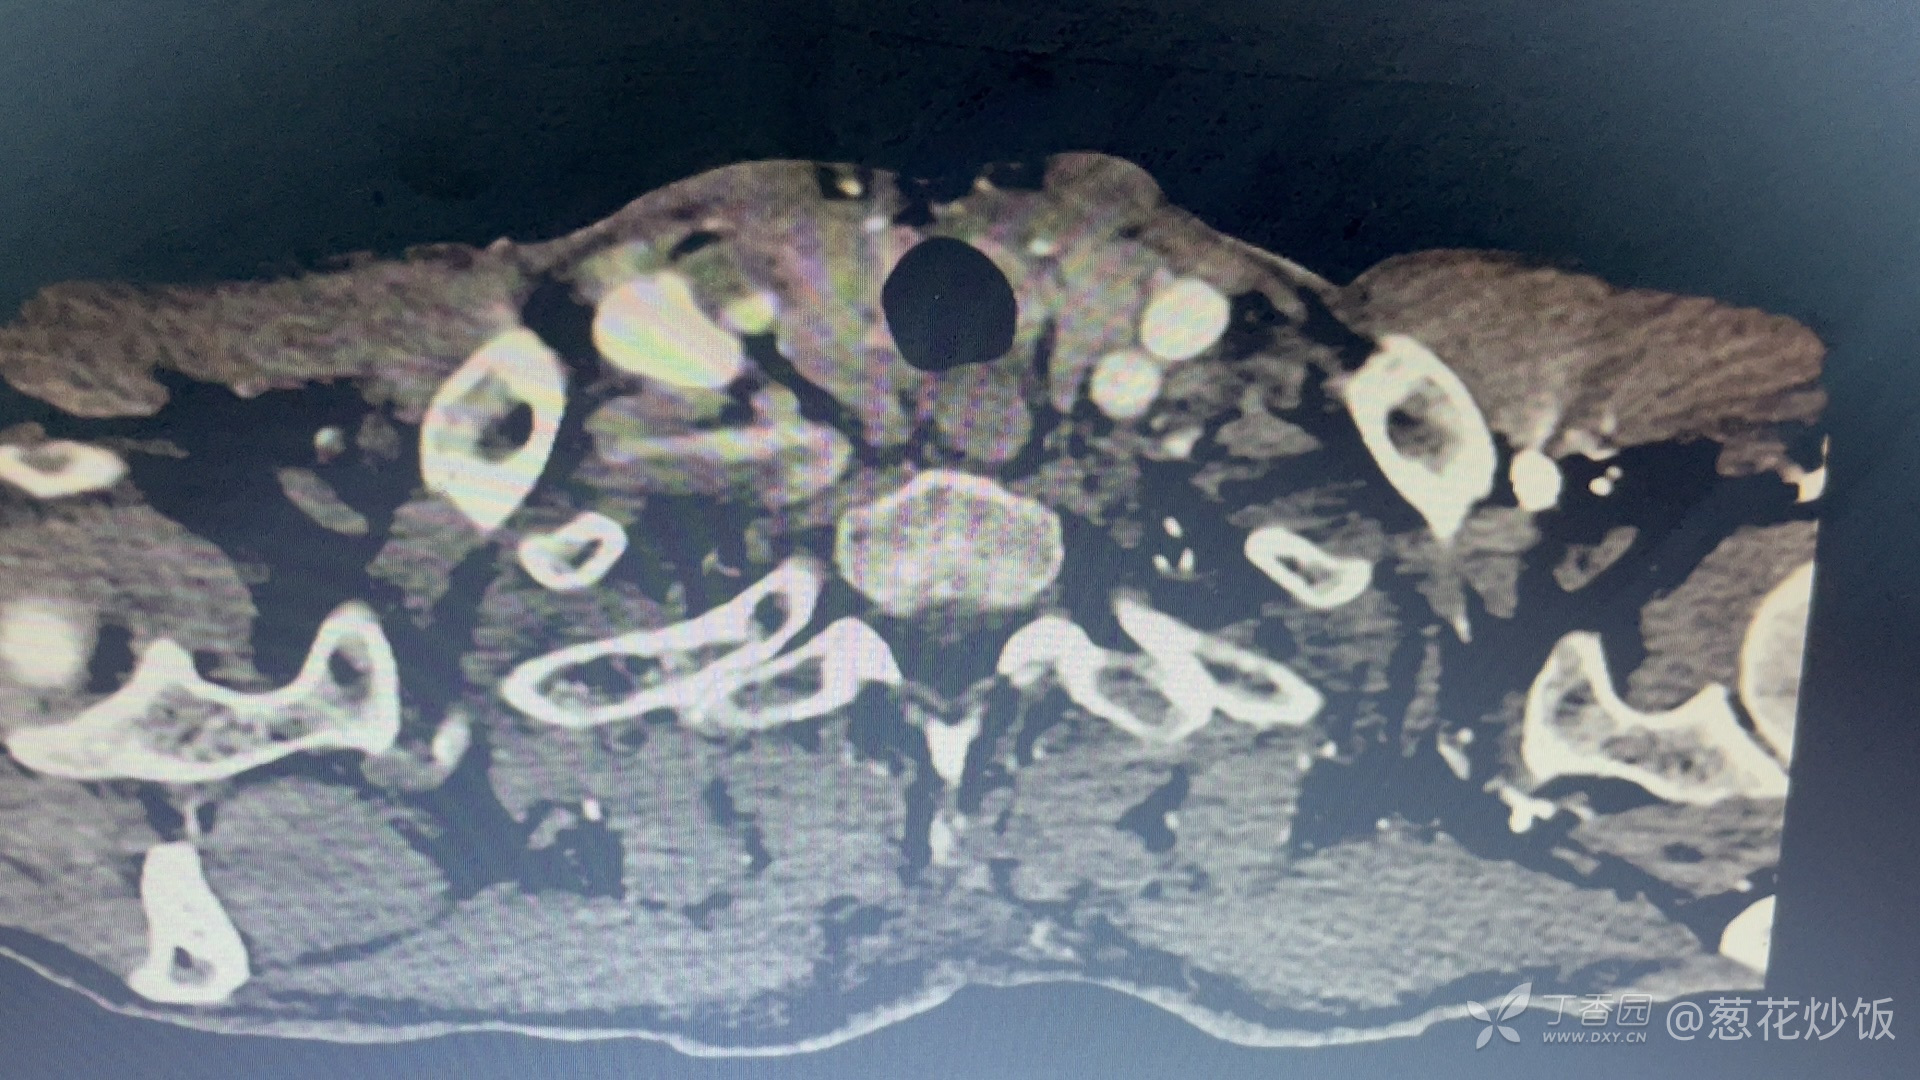

影像结果: